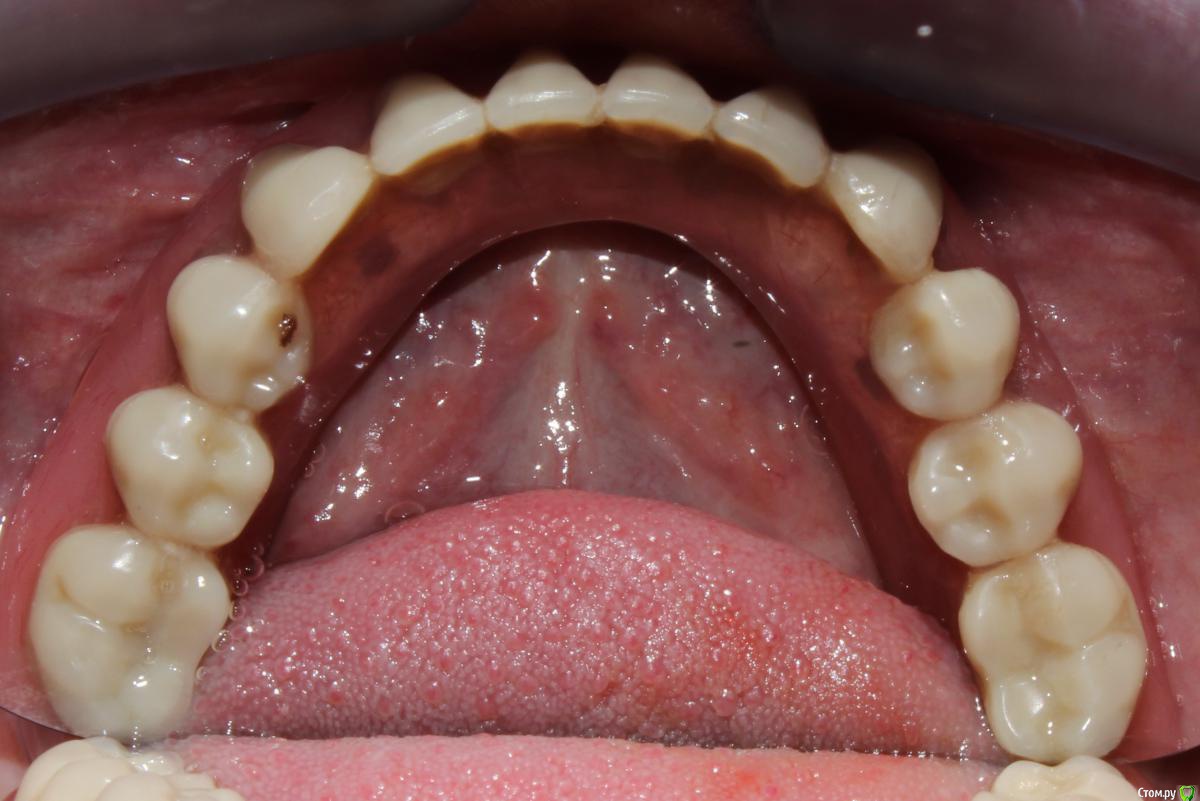

dr.Dre Опубликовано 1 февраля, 2016 Поделиться Опубликовано 1 февраля, 2016 Добрый день что это за система фиксации съёмников ? Ссылка на комментарий

Stomka Опубликовано 1 февраля, 2016 Поделиться Опубликовано 1 февраля, 2016 (изменено) я знаю, что это называется супрарадикулярный аттачмент.. по моему не тянет на громкое слово "система" Изменено 1 февраля, 2016 пользователем Stomka Ссылка на комментарий

Larnary Опубликовано 1 февраля, 2016 Поделиться Опубликовано 1 февраля, 2016 (изменено) Обычные Бреденты(или аналог) на вкладках. Реализация идеи ненадежная. Что касается протеза на нижнюю челюсть.Правильнее было бы сделать в протезе литую балку и вставить в нее матрицы. Изменено 1 февраля, 2016 пользователем Larnary Ссылка на комментарий

Ronin Опубликовано 1 февраля, 2016 Поделиться Опубликовано 1 февраля, 2016 У меня это просто культевые аттачменты по типу бредента, как упомянули ранее)) иногда приходится делать, когда финансы не позволяют разгуляться на другие виды конструкций или в свете атрофии и сопутствуещей патологии.. Зато лучше, чем просто съемник при диабете или частичный. А по поводу фиксации самих замков, то как вкладки, если нормально ставить, соблюдая протокол, то ничего не вылетает))) Ссылка на комментарий